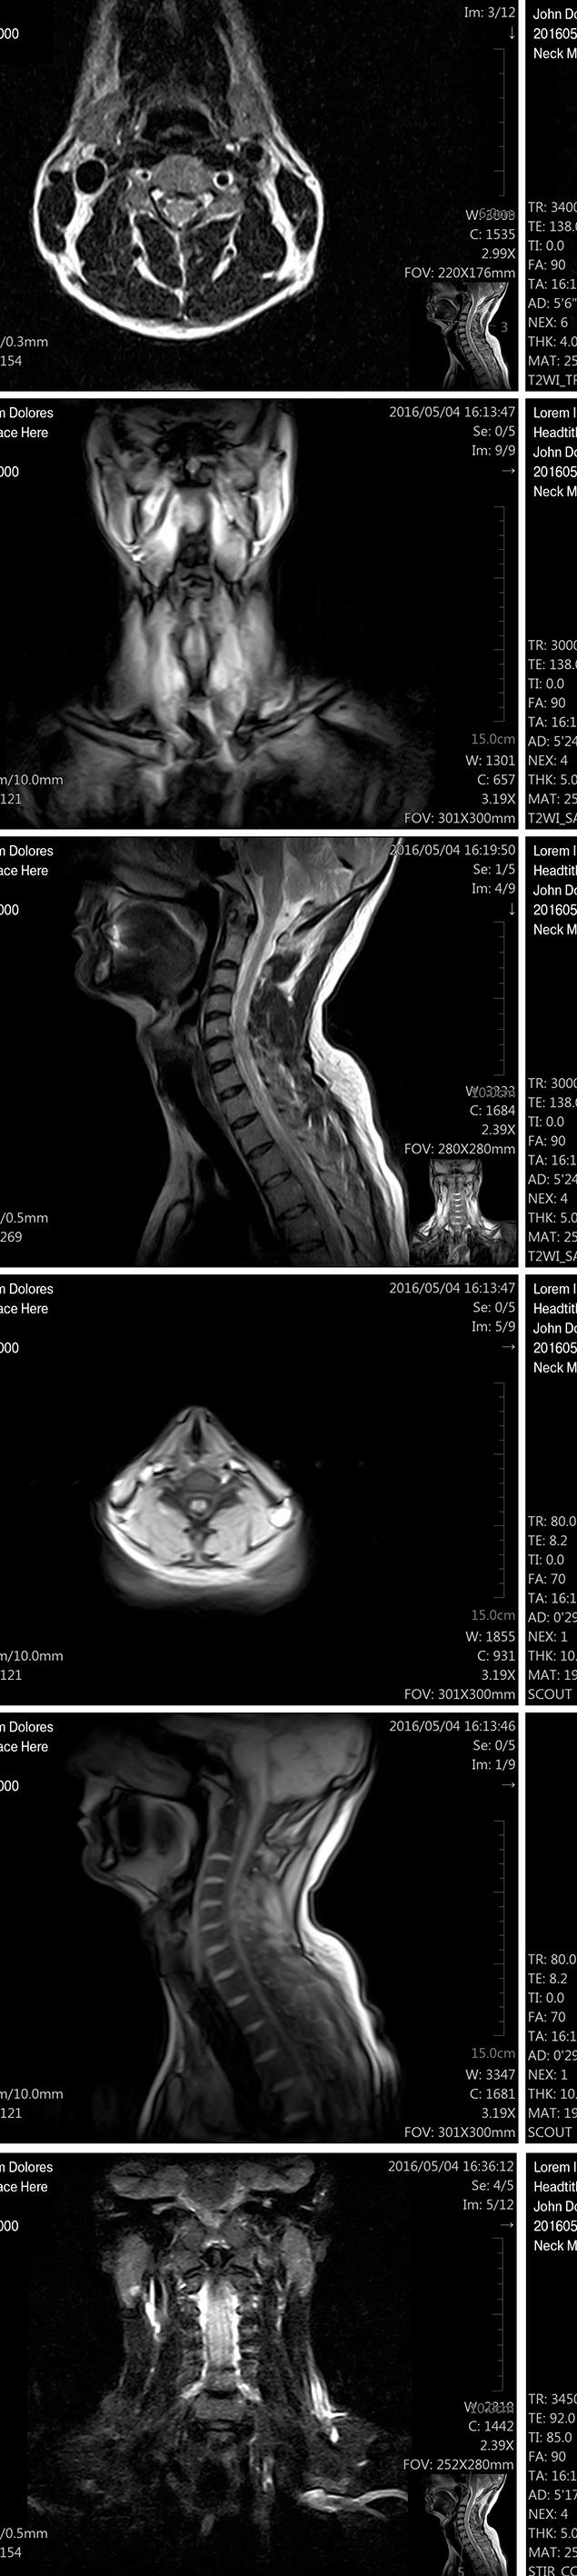

ISMRM: MRI detects brain changes in past cannabis users

If you’ve been following cannabis use and cannabis use disorder, you might not be surprised to learn that our most read story was about the heavy use of cannabis and its effect on the brain as detected by MRI. New Zealand researchers reported that heavy cannabis use is associated with structural brain changes

such as volumetric differences in subregions of the hippocampus and amygdala.